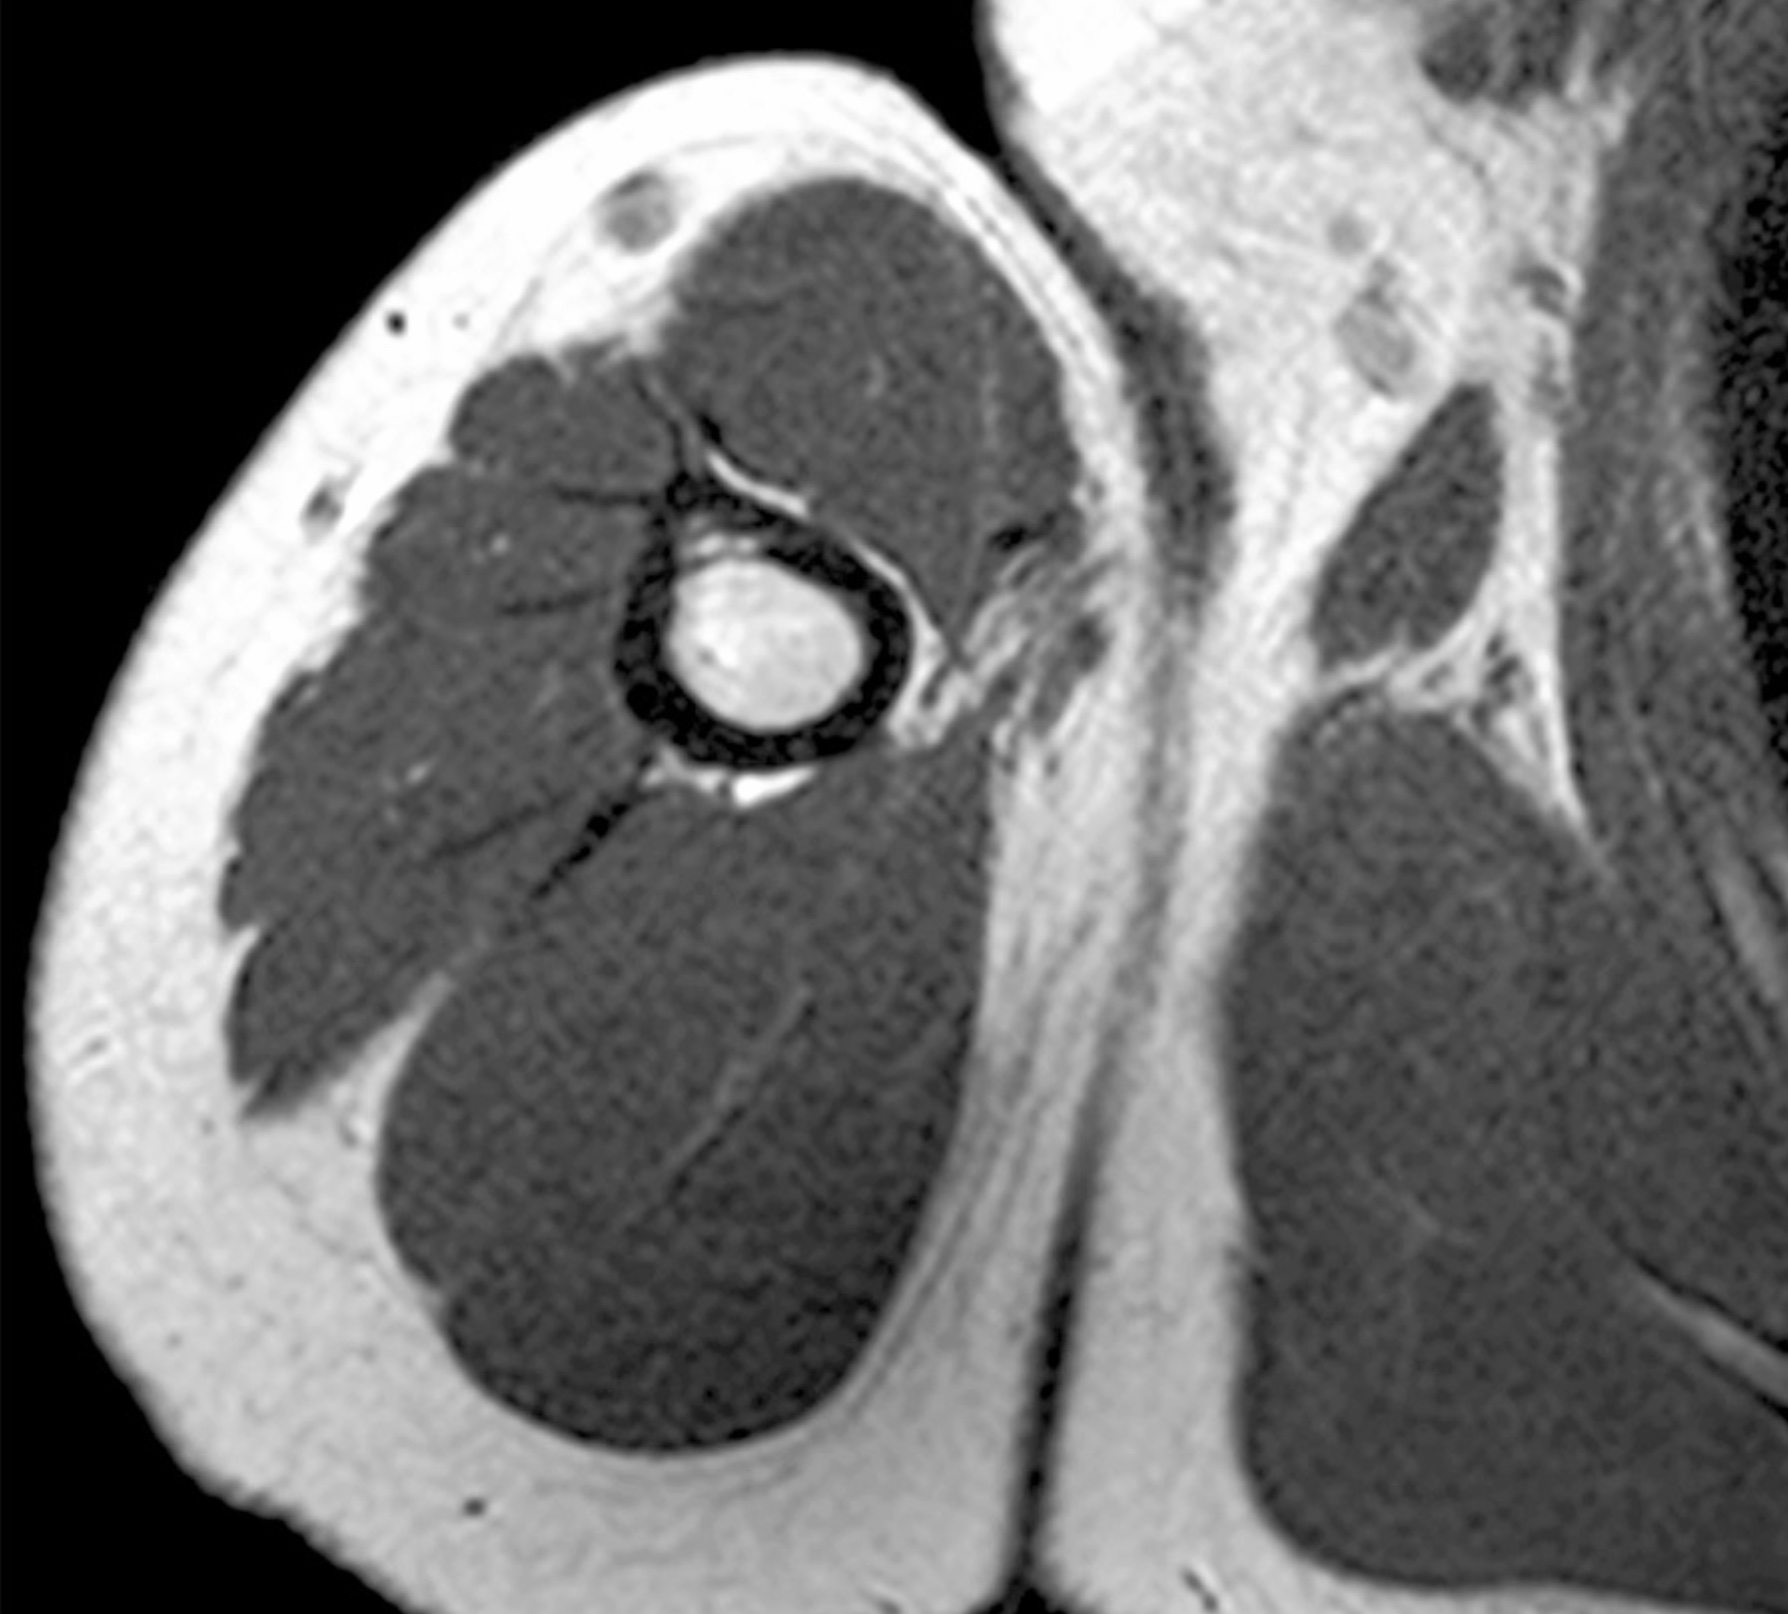

1. A 21 year old man presents to the clinic presenting weakened elbow extension, wrist drop and paresthesia of the posterior arm, lateral arm, dorsal forearm and hand. While you are gathering his history he mentions that it was his 21st birthday last night and had one too many to drink and ended up falling asleep while sitting on his living room table with his arm hanging over the back of the chair. Upon hearing this you diagnose the patient with Saturday night palsy. Discuss the anatomy of the radial nerve with regard to Saturday night palsy. Include structures associated with the pathway of the radial nerve and its branches through the upper limb, muscles, cutaneous branches. What classification of nerve injury would you give this injury and approximately how long will it be until the patient recovers?